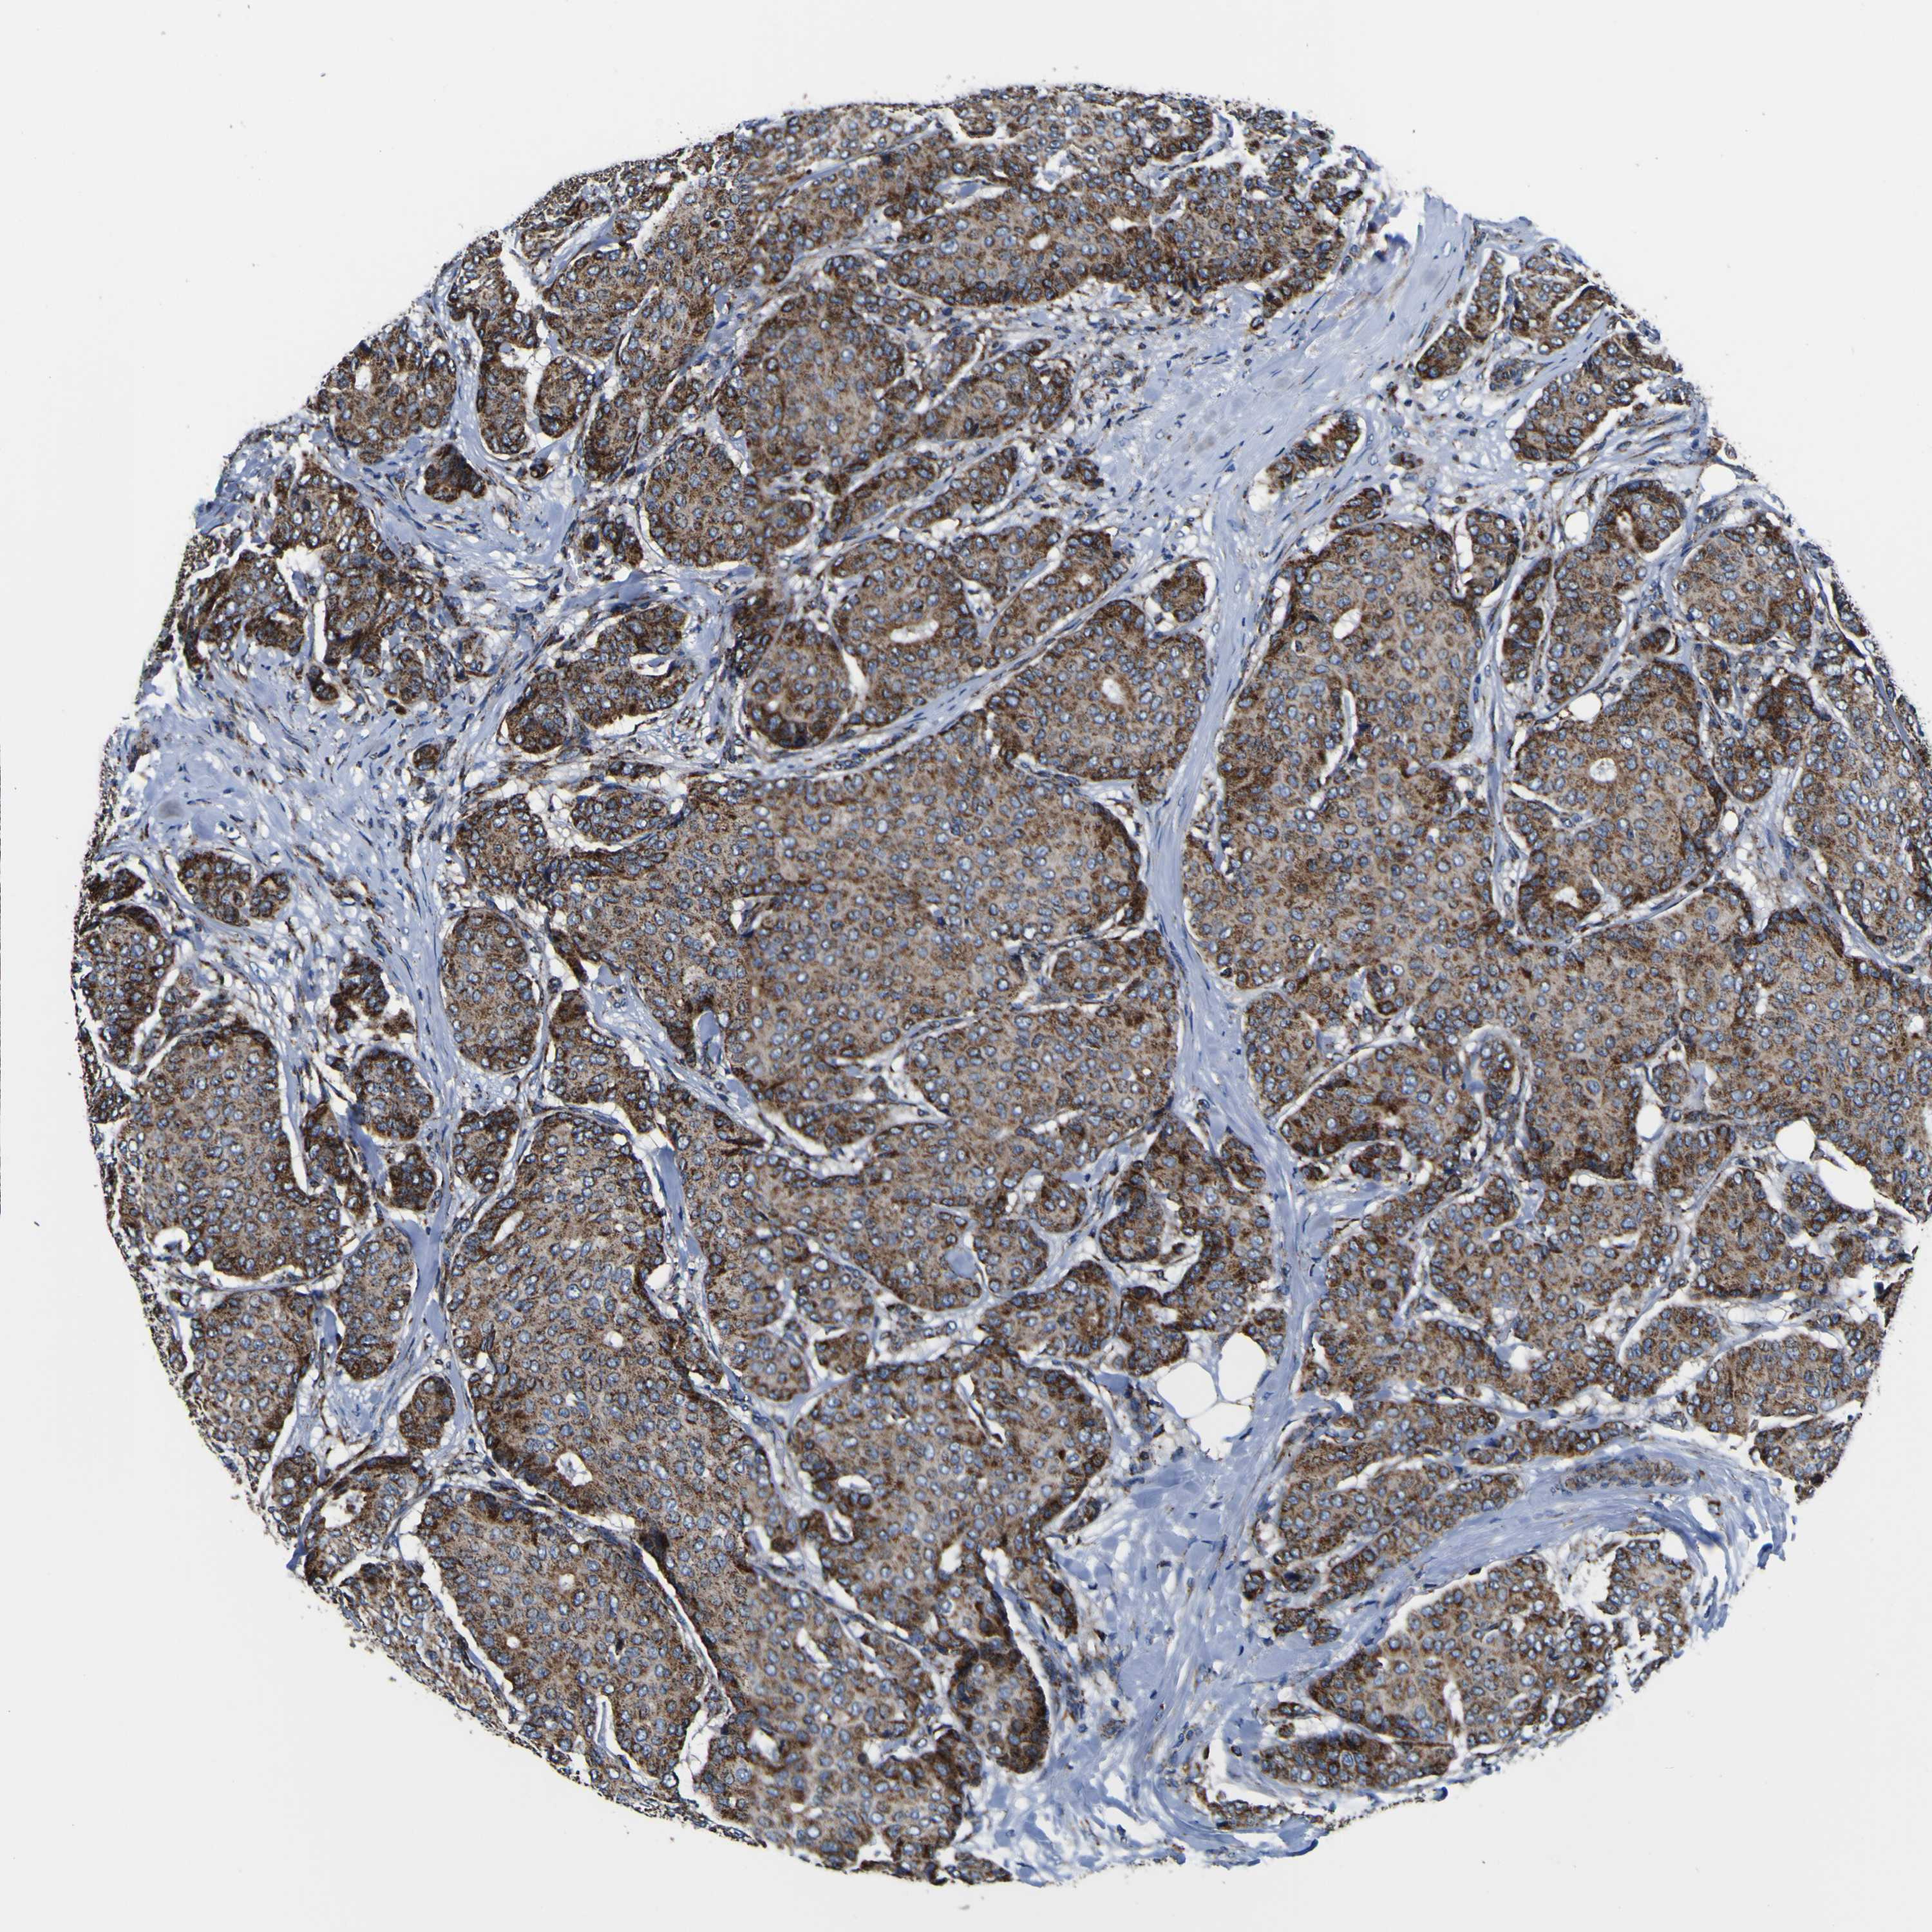

BRCA TCGA BRCA VALIDATION PROTEIN EXPRESSION